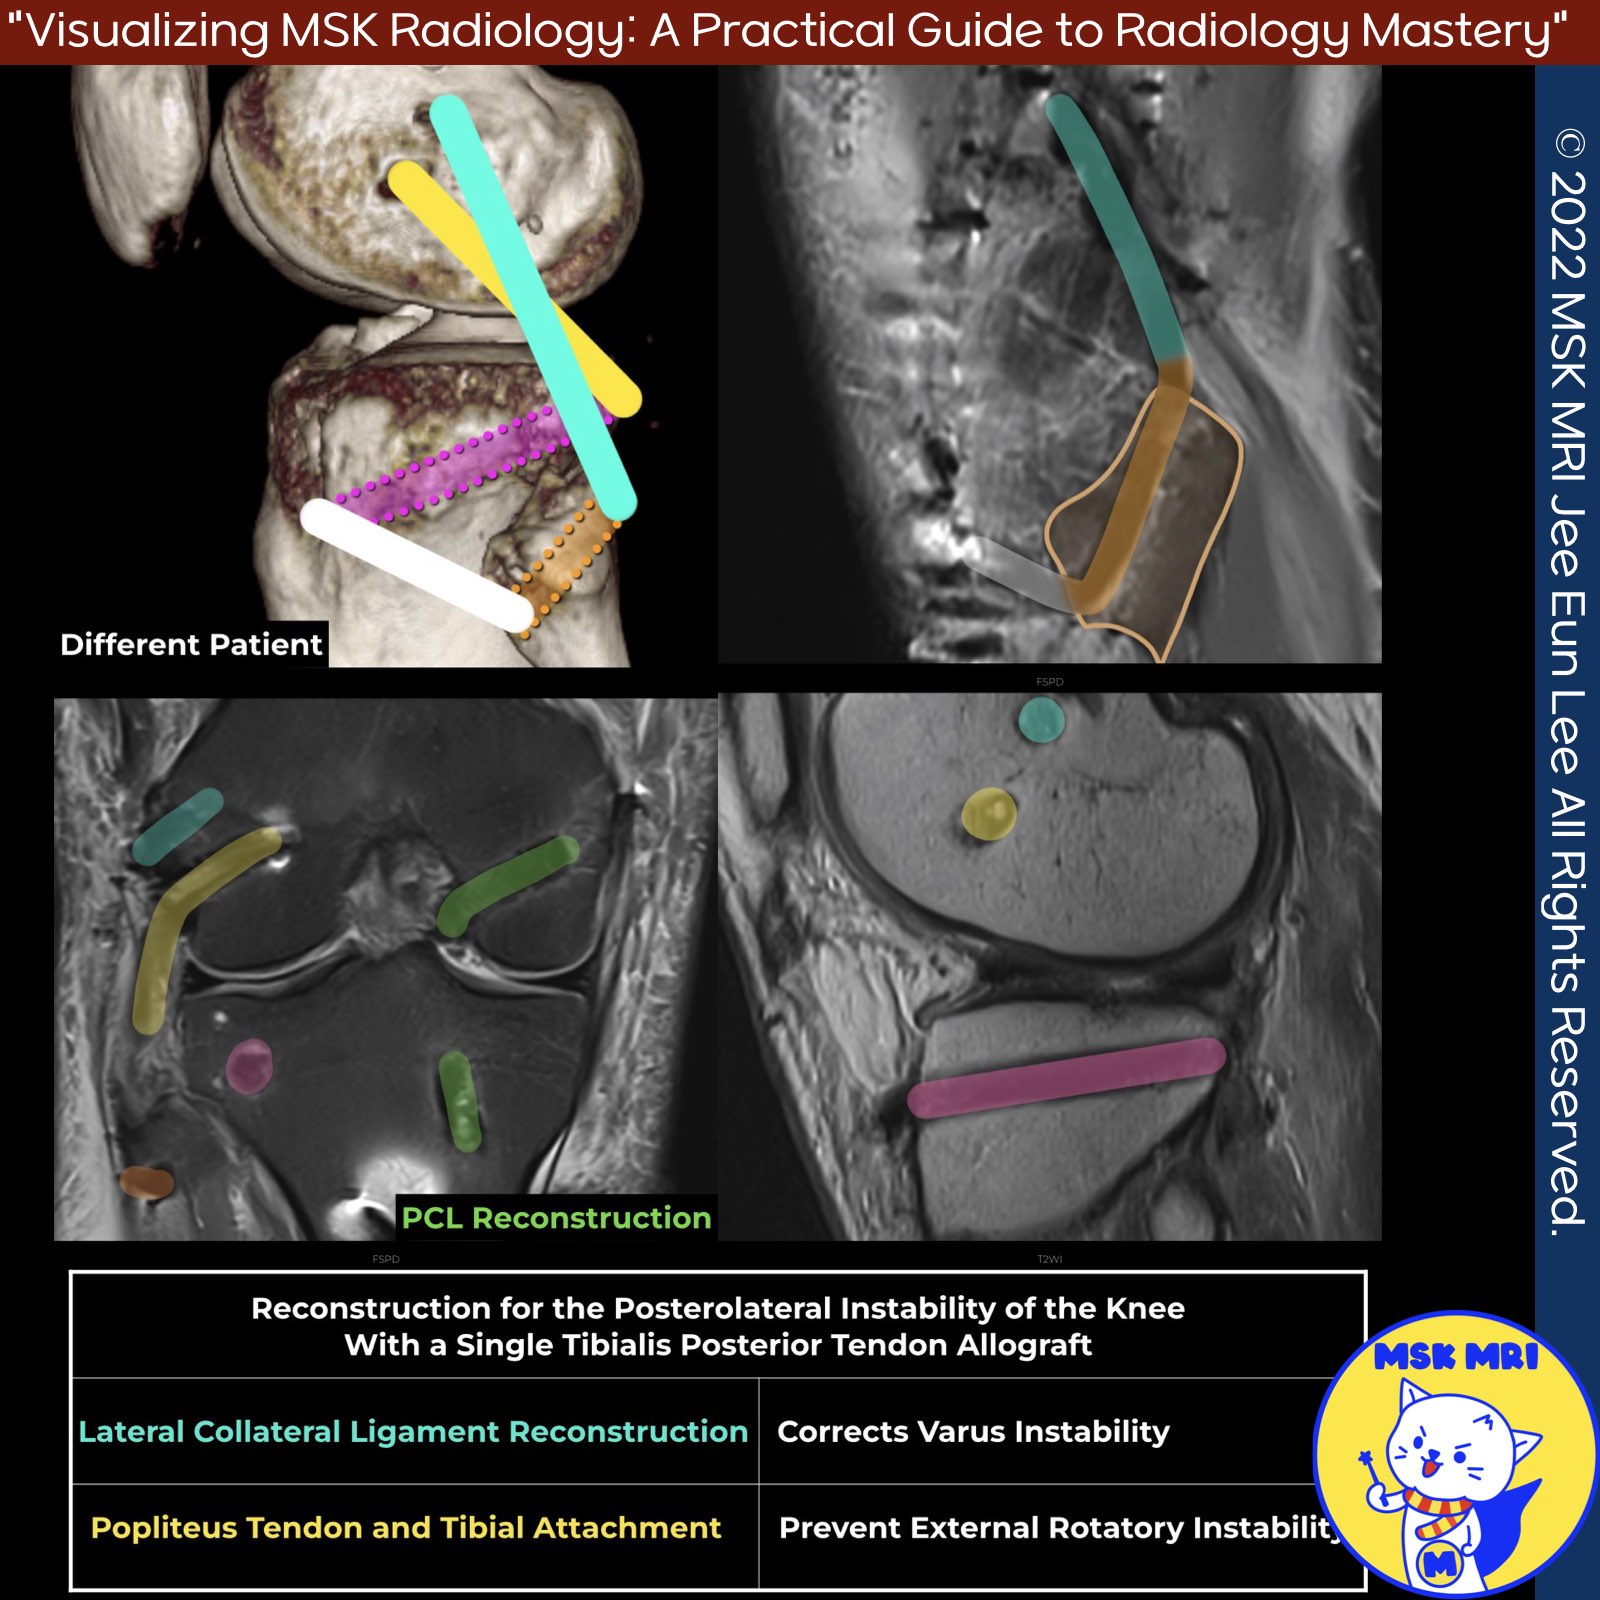

📌 Posterolateral Corner (PLC) Injury Treatment

- The lateral collateral ligament (LCL), popliteus tendon (PT), and popliteofibular ligament (PFL) are key reconstruction focus areas.

- Stannard’s Technique: Uses anterior or posterior tibial allografts (minimum 2.4 cm) to reconstruct the LCL, PT, and PFL.

- LaPrade’s Technique: Reconstruction of the LCL, PT, and PFL with two femoral tunnels, one tibial tunnel, and one fibular tunnel. Preferred graft is a split Achilles allograft.